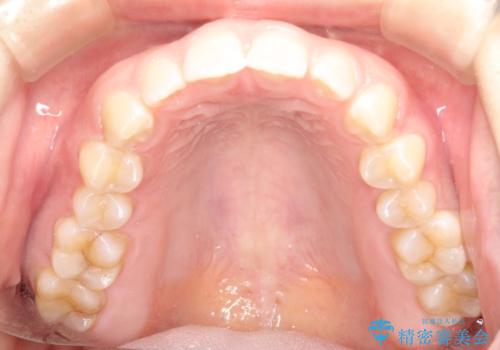

前歯の隙間を閉じたい インビザラインによる矯正

- 上下の前歯に隙間があるとのことで来院されました。

インビザラインにて隙間を閉じる矯正を行いました。